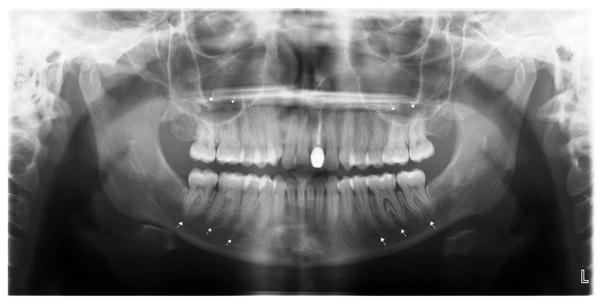

Fig. 1.

Panoramic radiograph of scleroderma patient with significant PLS widening, particularly in the mandibular and maxillary posterior teeth.

Table II shows that PLS widening of at least one tooth was noted in 38% of the patients with SSc compared with 11.1% of the controls (P < .001). Figures 1 and 2 show examples of widened PLS. This significant difference was confirmed by multivariate analysis adjusting for age, gender, ethnicity, education, and current smoking status (OR 6.56; 95% CI 3.52–12.21). There were significantly more teeth with PLS widening in patients with SSc than in controls in univariate (1.08 [SD 2.57] vs. 0.16 [SD 0.49]; P < .001) and multivariate (RR 7.72; 95% CI 4.45–13.38) analyses. The most significant differences between the two groups were found in the molars and premolars (P < .001) (see Table II).

There were significantly more patients with SSc with at least one site in the mandible with erosion compared with controls (14.5% vs. 3.6%; P < .001) (see Table II), and this was confirmed by multivariate analysis (OR 4.49; 95% CI 1.92–10.53). Figure 4 shows an example of mandibular erosions. The difference was most notable in the condyle (6.3% vs. 1.8%; P = .022), the coronoid process (5.0% vs. 0.5%; P = .005), and the other type of erosion (3.2% vs. 0%; P = .012). Results were not significant for the digastric region (P = .239). There was a trend toward more erosions in the posterior ramus in patients with SSc compared with controls (5.1% vs. 1.4%; P = .058) (see Table II). With regard to the mean of the patients with SSc with erosions, 60.9% had more than one erosion in their mouths, and the mean number of erosions was 2.09 (SD 1.16).

Panoramic radiograph of scleroderma patient with severe erosions at (A) the coronoid processes, (B) the angles of the mandible. Also shown: PLS widening in (C) maxillary posterior teeth, and (D) mandibular posterior teeth.

In our study of 163 patients with SSc and 231 controls, we found that patients with SSc tend to have significantly more teeth with widening of the PLS and more mandibular erosions (see Figures 1 and 4). Our findings add substantially to the knowledge in the literature, as none of the previous studies of the estimates of the prevalence of radiographic abnormalities in the jaws in SSc systematically studied all suspected SSc radiographic manifestations (Table III). In addition, the number of patients examined in these studies was generally small, between 15 and 47,12–14,17,18,26–29 and controls were used in only seven studies.12–18 Another limitation of the previous studies is that the controls were either selected from patients attending the dental clinic,14 hospital staff,14 or patients with inflammatory diseases, such as rheumatoid arthritis and systemic lupus erythematosus.18 Prevalence estimates had been documented by using a convenience sample in some studies; consequently, selection and information bias may have affected the internal validity of these results. This may have biased these studies against finding abnormalities in the patients with SSc, potentially underestimating the true increased prevalence of oral disease compared with the general population (see Table III).